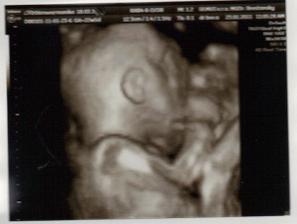

✿♥♥♥♥Bude to dievčatko!!!!! ♥♥♥♥✿

Bude to Stella 🙂

krasne 3D sono 🙂